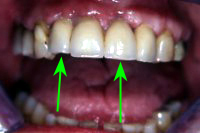

Die Teilprothese wurde während der Einheilphase der Implantate provisorisch getragen und jeweils angepasst. Die Patientin war nie ohne Zähne. Abb. 2 zeigt die dreigliedrige Fontbrücke auf zwei Implantaten zementiert und zwei Seitenzähne auf zwei Implantaten zementiert. Der eigene Eckzahn zwischen den beiden Implantatbrücken konnte erhalten werden (Abb. 3, grüner Pfeil).